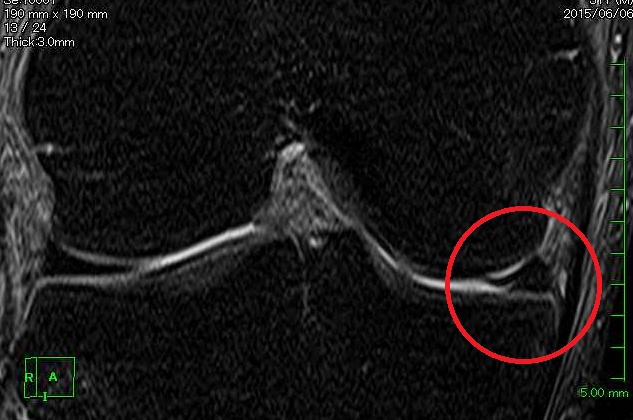

落書きのお尻ではありません。私の膝のMRI画像です。

改めて見てみると、やっぱり半月板と思しき場所が割れていますよね。

2015年6月に撮ったものですから最初に受傷したときでしょう。

こんな状態でよく手術しないで復帰しようと思いましたよね。